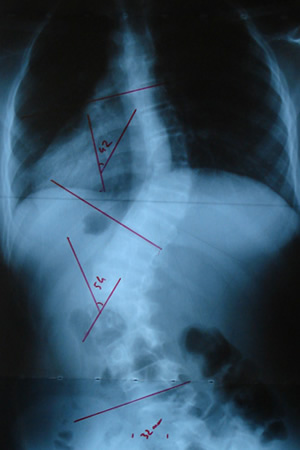

Grafilerle Skolyoz